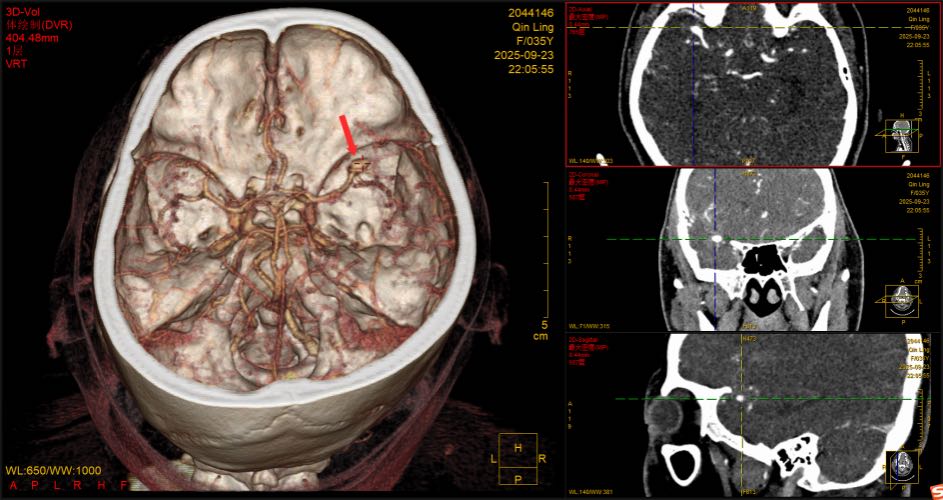

9月24日0:30左右,一场与时间赛跑的抢救正在手术室悄然进行中。9月23日22:00时许,35岁的覃女士因“突感头晕头痛,恶心呕吐”不适,家人呼叫120救护车送至深圳市中西医结合医院急诊科抢救室。急诊科救治团队迅速展开一系列抢救和检查,患者为右侧大脑中动脉动脉瘤破裂出血,病情紧急。此时,正值“桦加沙”超强台风防御期,脑外科的张力主任、朱美蓉护士长以及全体值班、备班、二线的医生,正在科室留守,以应对各种突发事件。接到急诊科抢救室会诊通知后,张力主任团队迅速响应。张力主任介绍,患者既往有高血压病史,CT检查结果有动脉瘤破裂出血,且动脉瘤较大,形态不规则,再出血风险较大,一旦再出血后果将不堪设想,需尽快进行急诊开颅手术治疗。

红色箭头处为动脉瘤。

患者家属同意手术后,9月24日0:30左右,在麻醉科和手术室的协助下,由宝安区神经外科首席专家张力主任主刀,值班医生刘裕浩副主任医师密切配合,为患者进行紧急开颅脑动脉瘤夹闭手术。经过近7个小时的努力,顺利完成手术,成功为患者摘除颅内“炸弹”。患者被送入脑外科重症监护病房进行监护治疗。目前,患者已脱离生命危险。